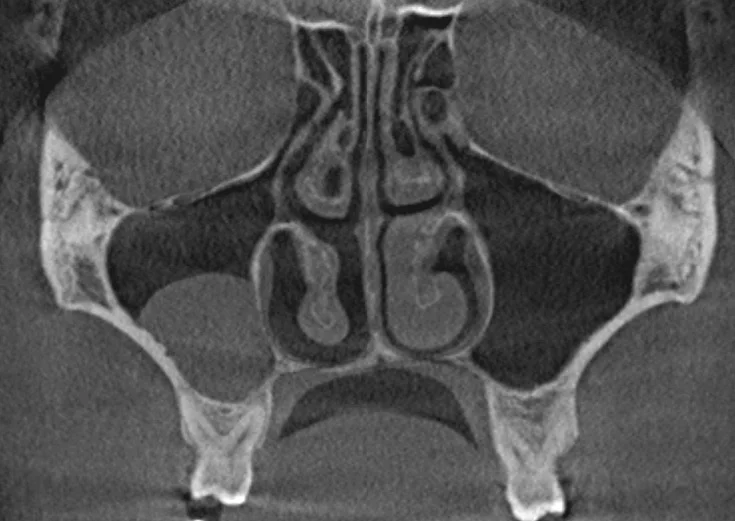

- заболевания пазух верхней челюсти;

| Челюстно-лицевая хирургия: | ЛОР-диагностика : | ||

| Диагностика и оценка переломов челюстно-лицевой области (средней и нижней зон лица). | Диагностика воспалительных заболеваний и новообразований всех придаточных пазух носа (в т.ч. верхнечелюстные синусы). | ||